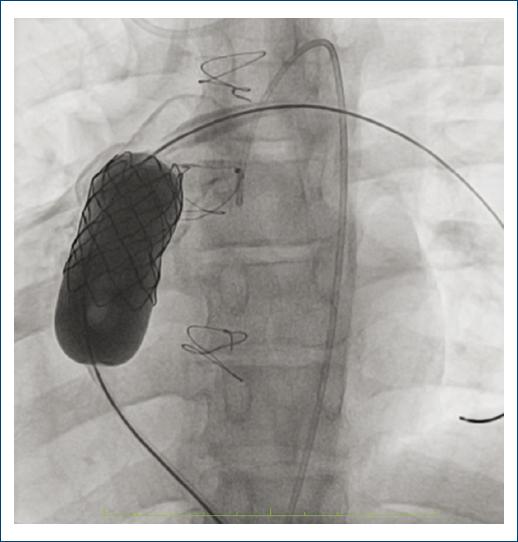

Se efectúa cateterismo cardíaco derecho e izquierdo, con acceso femoral percutáneo. Se utiliza un catéter wedge para medir las presiones en la circulación derecha y un catéter helicoidal para angiografías en el VD. Se realiza intercambio por una guía Lunderquist de 0.35 x 260 cm y sobre ésta se avanza un balón Atlas, el cual se expande en el tracto de salida del VD con coronariografía selectiva simultánea para descartar una compresión extrínseca (Fig. 2). El tracto de salida y el homoinjerto se preparan con implantación de un stent cubierto CP sobre un balón Numed BIB (balloon in balloon), como se muestra en la figura 3. Luego se prepara la válvula Melody (en uno de los casos tras acoplar un stent Andra XL adicional sobre esta prótesis) y se avanza con el sistema ENSAMBLE hasta la landing zone creada con el CP stent cubierto. Se infla el balón interno, se verifica una posición adecuada (Fig. 4) y luego se infla el externo para incidir de manera satisfactoria en la válvula. Se obtienen angiografías de control en la arteria pulmonar y el ventrículo derecho (Fig. 4) y se repiten las coronariografías de control para descartar compresión. Los principales resultados obtenidos en el laboratorio de hemodinamia se presentan en la tabla 1 y para cada uno de los pacientes notificados.

Figura 4 Imagen de válvula Melody implantada. Angiografía del conducto del tracto de salida del ventrículo derecho. Verificación de una posición adecuada de la válvula implantada.